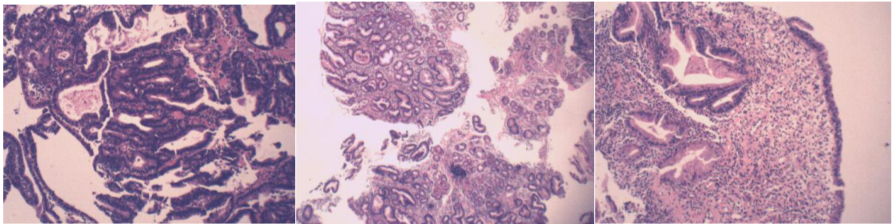

2018-3-14经皮肝穿病理:符合胃癌并肝转移。

病理示:(肝)癌。

免疫组化结果:Glypican-3(-),Hepatocyte(-)不支持肝细胞癌,NapsinA(-),TTF-1(-),不支持肺癌转移;CEA(+),CK(+),CK19(+),CK20(-)CK7(+)。

2018-3-19会诊外院胃病理

(胃)中-低分化腺癌,取材浅,组织碎,未知深部浸润情况;

免疫组化:P21(-/+),CEA(+),P53(+),Ki67阳性率约为60%,D2-40(-),HER2(2+);

HER2荧光原位杂交检测结果判读:HER2基因有扩增